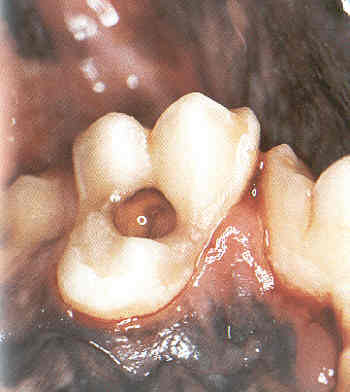

Karies

Karies tritt beim Hund selten auf. Bei früher Entdeckung dann der betroffene Zahn gerettet werden.